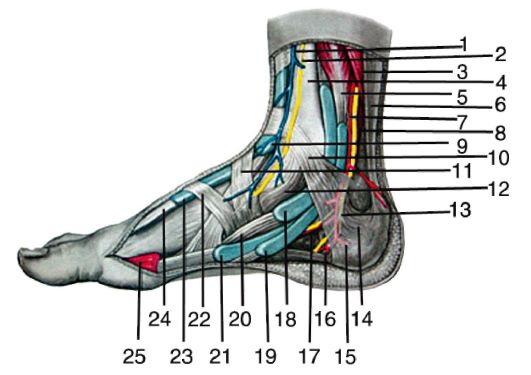

Анатомия голеностопа: Сухожилия и их строение